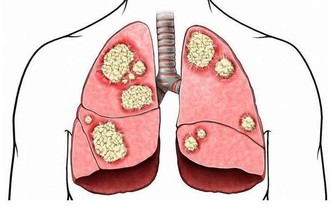

大家都知道,心血管疾病是中老年人健康的第一大殺手,